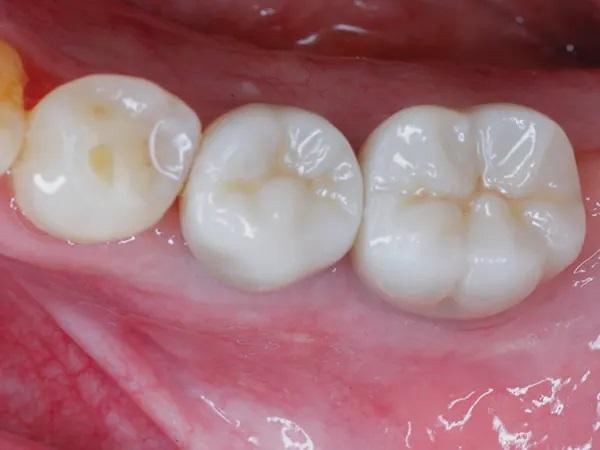

КЛКТ-снимок был выполнен перед повторным посещением через 6 месяцев, и на нем была видна достаточная высота и ширина кости для установки имплантата (Фото 16). При полном откидывании лоскута было обнаружено значительное увеличение ширины альвеолярного гребня в этом месте (Фото 17 и Фото 18). Установку имплантата (Straumann Bone Level Tapered Implant, 3,3 мм x 12 мм, Straumann) завершили, а индивидуальный формирователь десны затянули вручную, чтобы создать идеальный профиль выступания (Фото 19). На имплантат была установлена керамическая коронка с винтовой фиксацией через 4 месяца после установки имплантата (Фото 20).

Фото 20: Окончательная реставрация, вид с буккальной стороны, 4 месяца после установки имплантата.